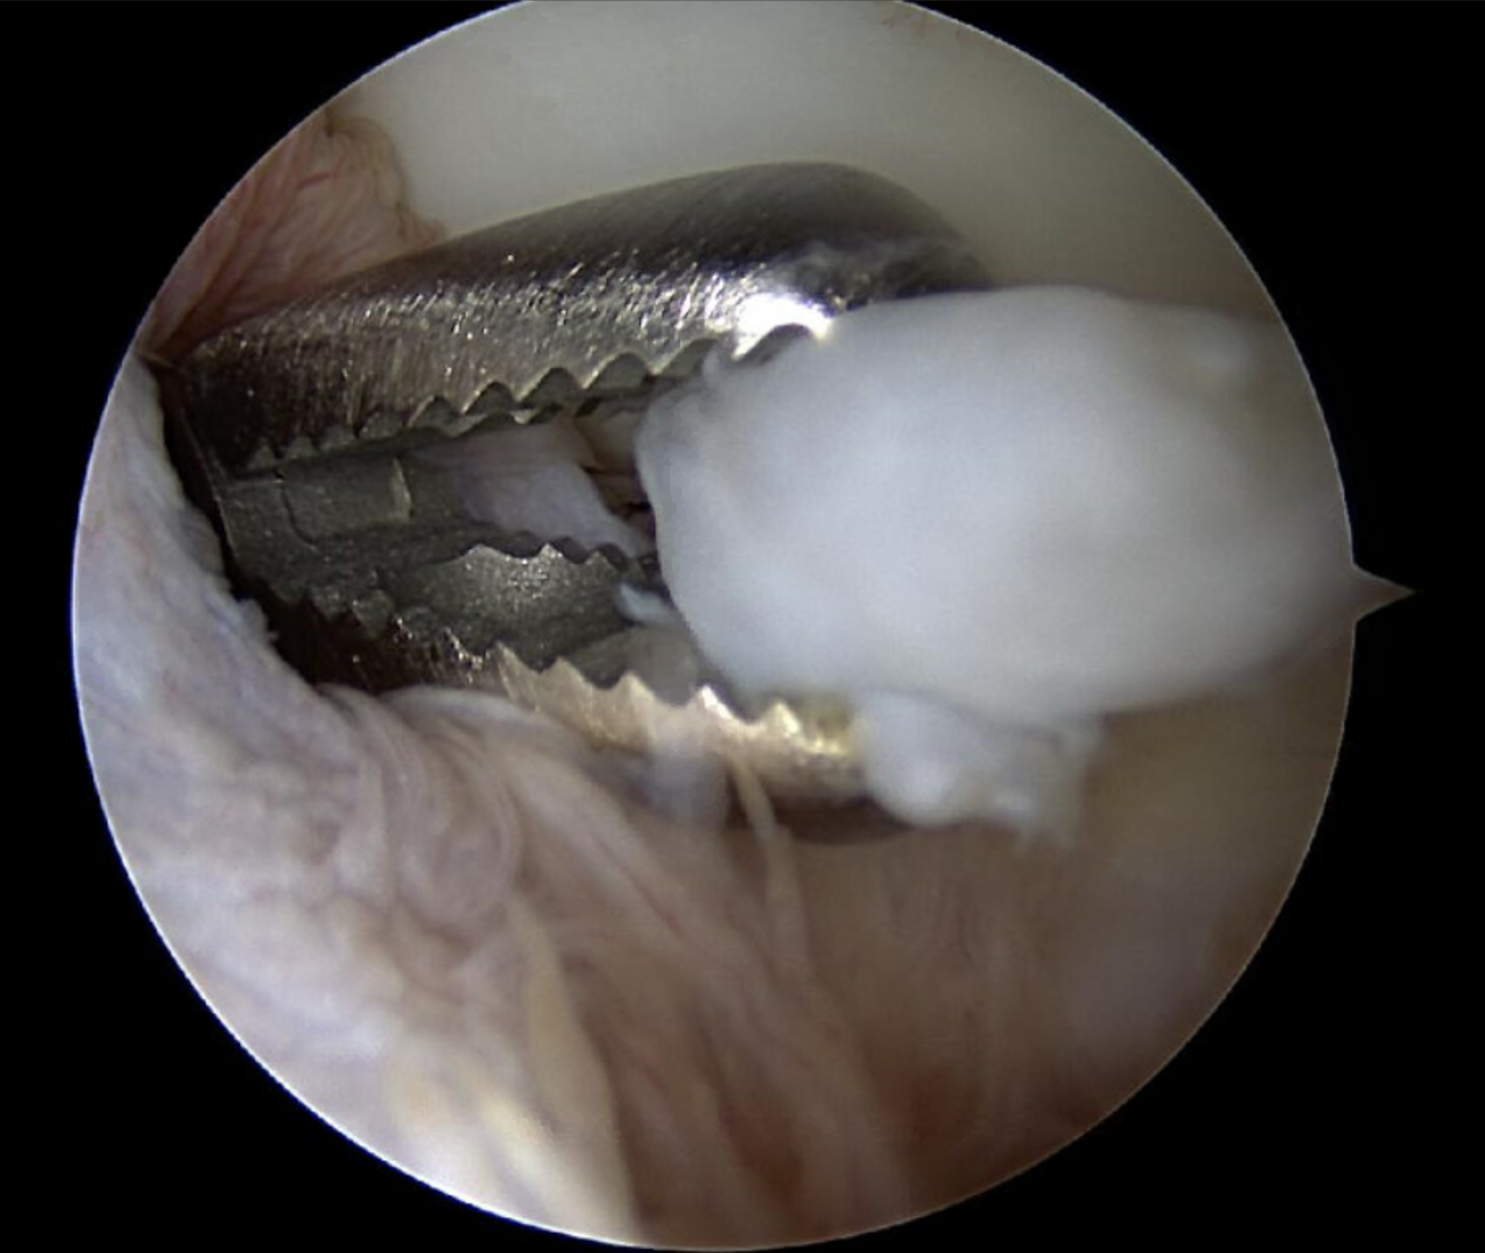

Deze ingreep kan enkel onder algemene anesthesie gebeuren. De patiënt ligt op zijn/haar zij, en via enkele kleine steekgaatjes wordt een camera en een werkinstrument het gewricht in gebracht. Op deze manier kan onder zicht het nodige gebeuren zonder dat grote incisies nodig zijn. Zo kan bijvoorbeeld de pees die de tenniselleboog veroorzaakt proper gemaakt worden, bepaalde inklemmende gewrichtsplooien of botfragmenten worden verwijderd. Meestal worden er 5 gaatjes gebruikt, maar dit kan naar gelang van de operatie ook wel eens een meer of minder zijn.